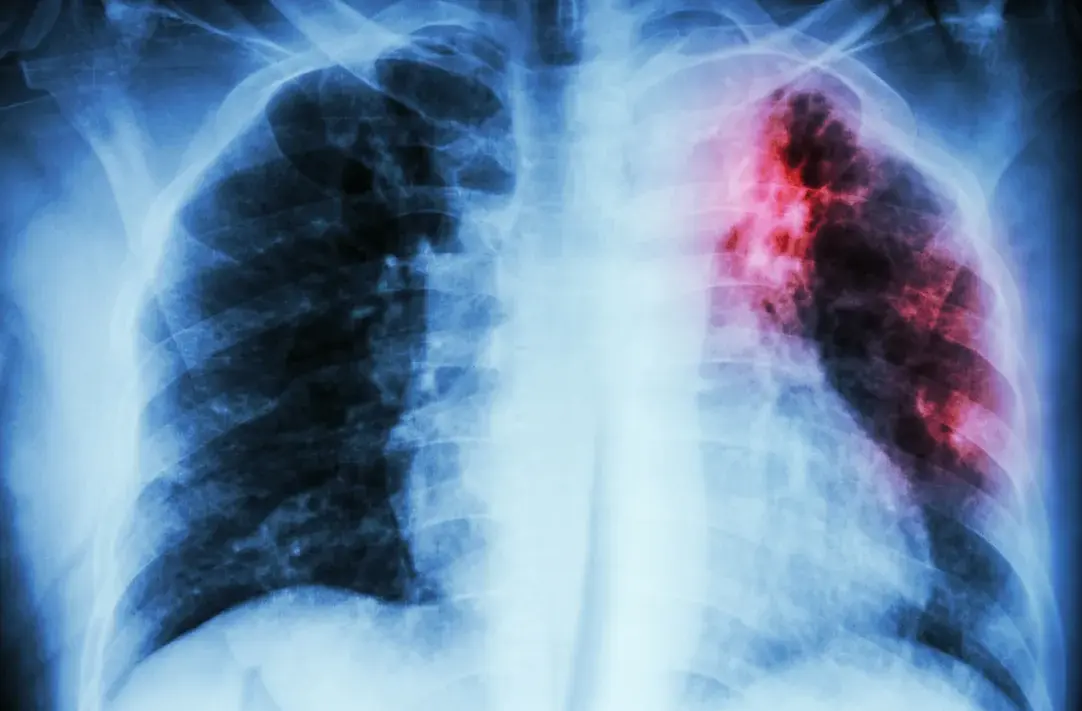

“The name for tuberculosis actually comes from tubercles,” small lesions in the lungs caused by the disease, says Dionne, associate clinical professor in pharmacy and health systems science.

“It can start to destroy lung tissue,” he says. “When most people die of tuberculosis, it’s actually from tissue deterioration and respiratory failure.”